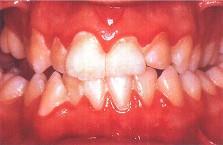

问题 下列哪项不是慢性龈缘炎的临床表现()

选项 A.牙龈充血肿胀 B.探诊龈沟出血 C.龈沟深度超过3mm D.牙周附着丧失 E.无牙槽骨吸收

答案 D